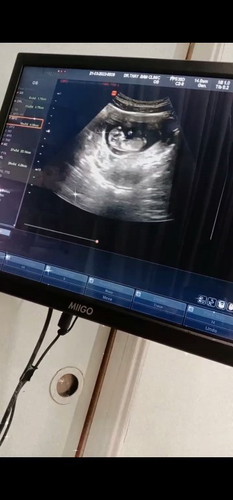

หมอนัดตรวจรอบ2 12สัปดาห์แล้วจ้าา ตื่นเต้นมาก แล้วคิดมาก เพราะแม่ตอนเช้า ตื่นที 9โมงเกือบ10โมง กว่าจะได้กินข้าวเช้า แต่พอหมอบอกลูกดูดสารอาหารได้ดี ก็ดีใจแล้วจ้าา🤣🤣